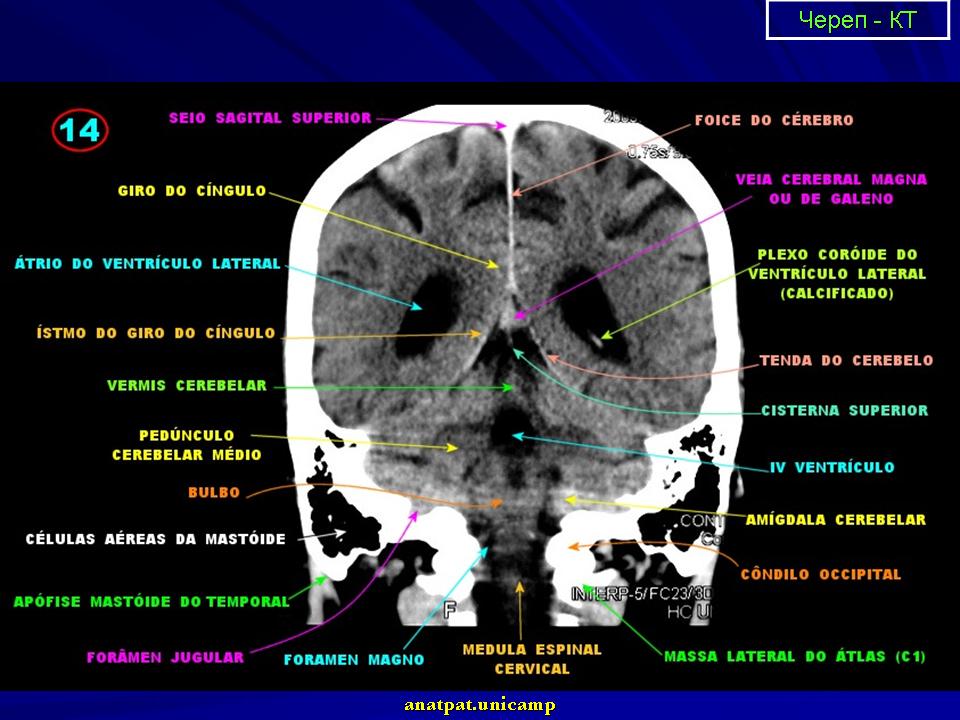

Нормальная КТ - анатомия головного мозга.

1.ki_.slayd1_.jpg2.ki_.slayd2_.jpg3.ki_.slayd3_.jpg4.ki_.slayd4_.jpg5.ki_.slayd5_.jpg6.ki_.slayd6_.jpg7.ki_.slayd7_.jpg8.ki_.slayd8_.jpg11.ki_.slayd9_.jpg12.ki_.slayd10.jpg13.ki_.slayd11.jpg14.ki_.slayd12.jpg15.ki_.slayd13.jpg16.ki_.slayd14.jpg17.ki_.slayd15.jpg18.ki_.slayd16.jpg21.ki_.slayd17.jpg22.ki_.slayd18.jpg23.ki_.slayd19.jpg24.ki_.slayd20.jpg25.ki_.slayd21.jpg26.ki_.slayd22.jpg27.ki_.slayd23.jpg28.ki_.slayd24.jpg